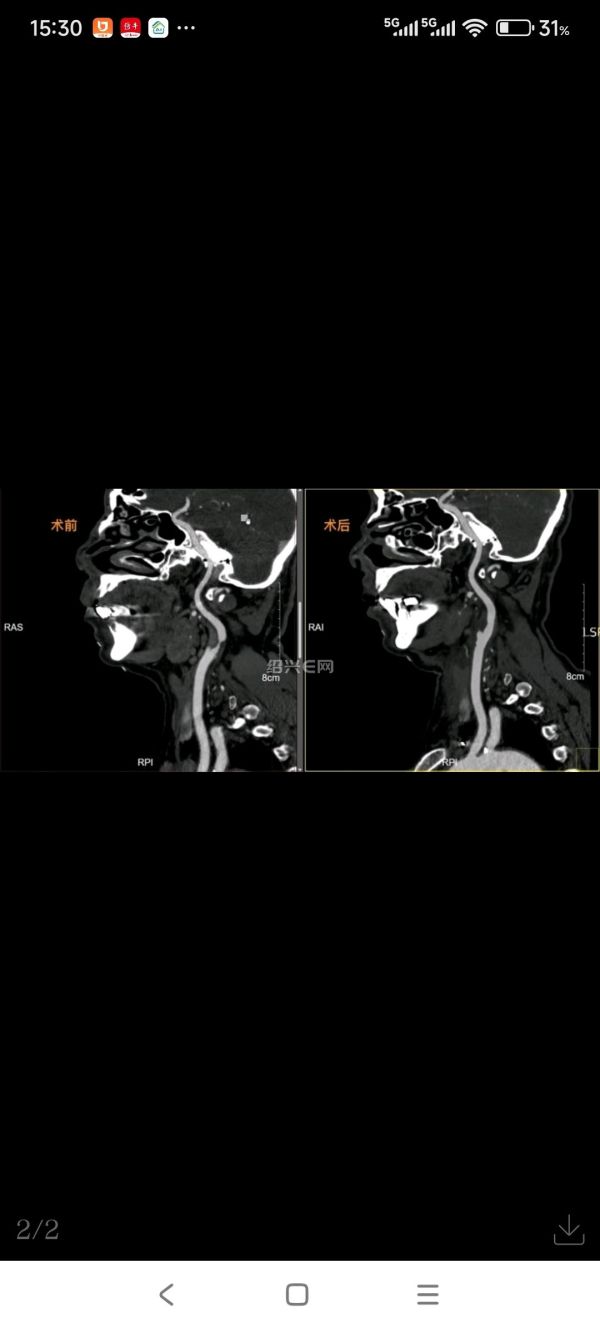

经评估,孙伟军主任及彭德清副主任医师决定先做左侧的颈动脉手术。术中,完整切除导致颈动脉重度狭窄的斑块,并清除干净斑块碎屑,防止血管再通后斑块脱落导致新的卒中。术后第二天,老费就能坐起来并能下床活动,术前随时发生晕倒的情况再也没出现。检查也证实,他左侧颈动脉已完全通畅,脑供血也明显改善。

术后第6天老费出院。一个多月后,孙伟军主任等将他右侧堵塞的颈动脉也顺利开通。